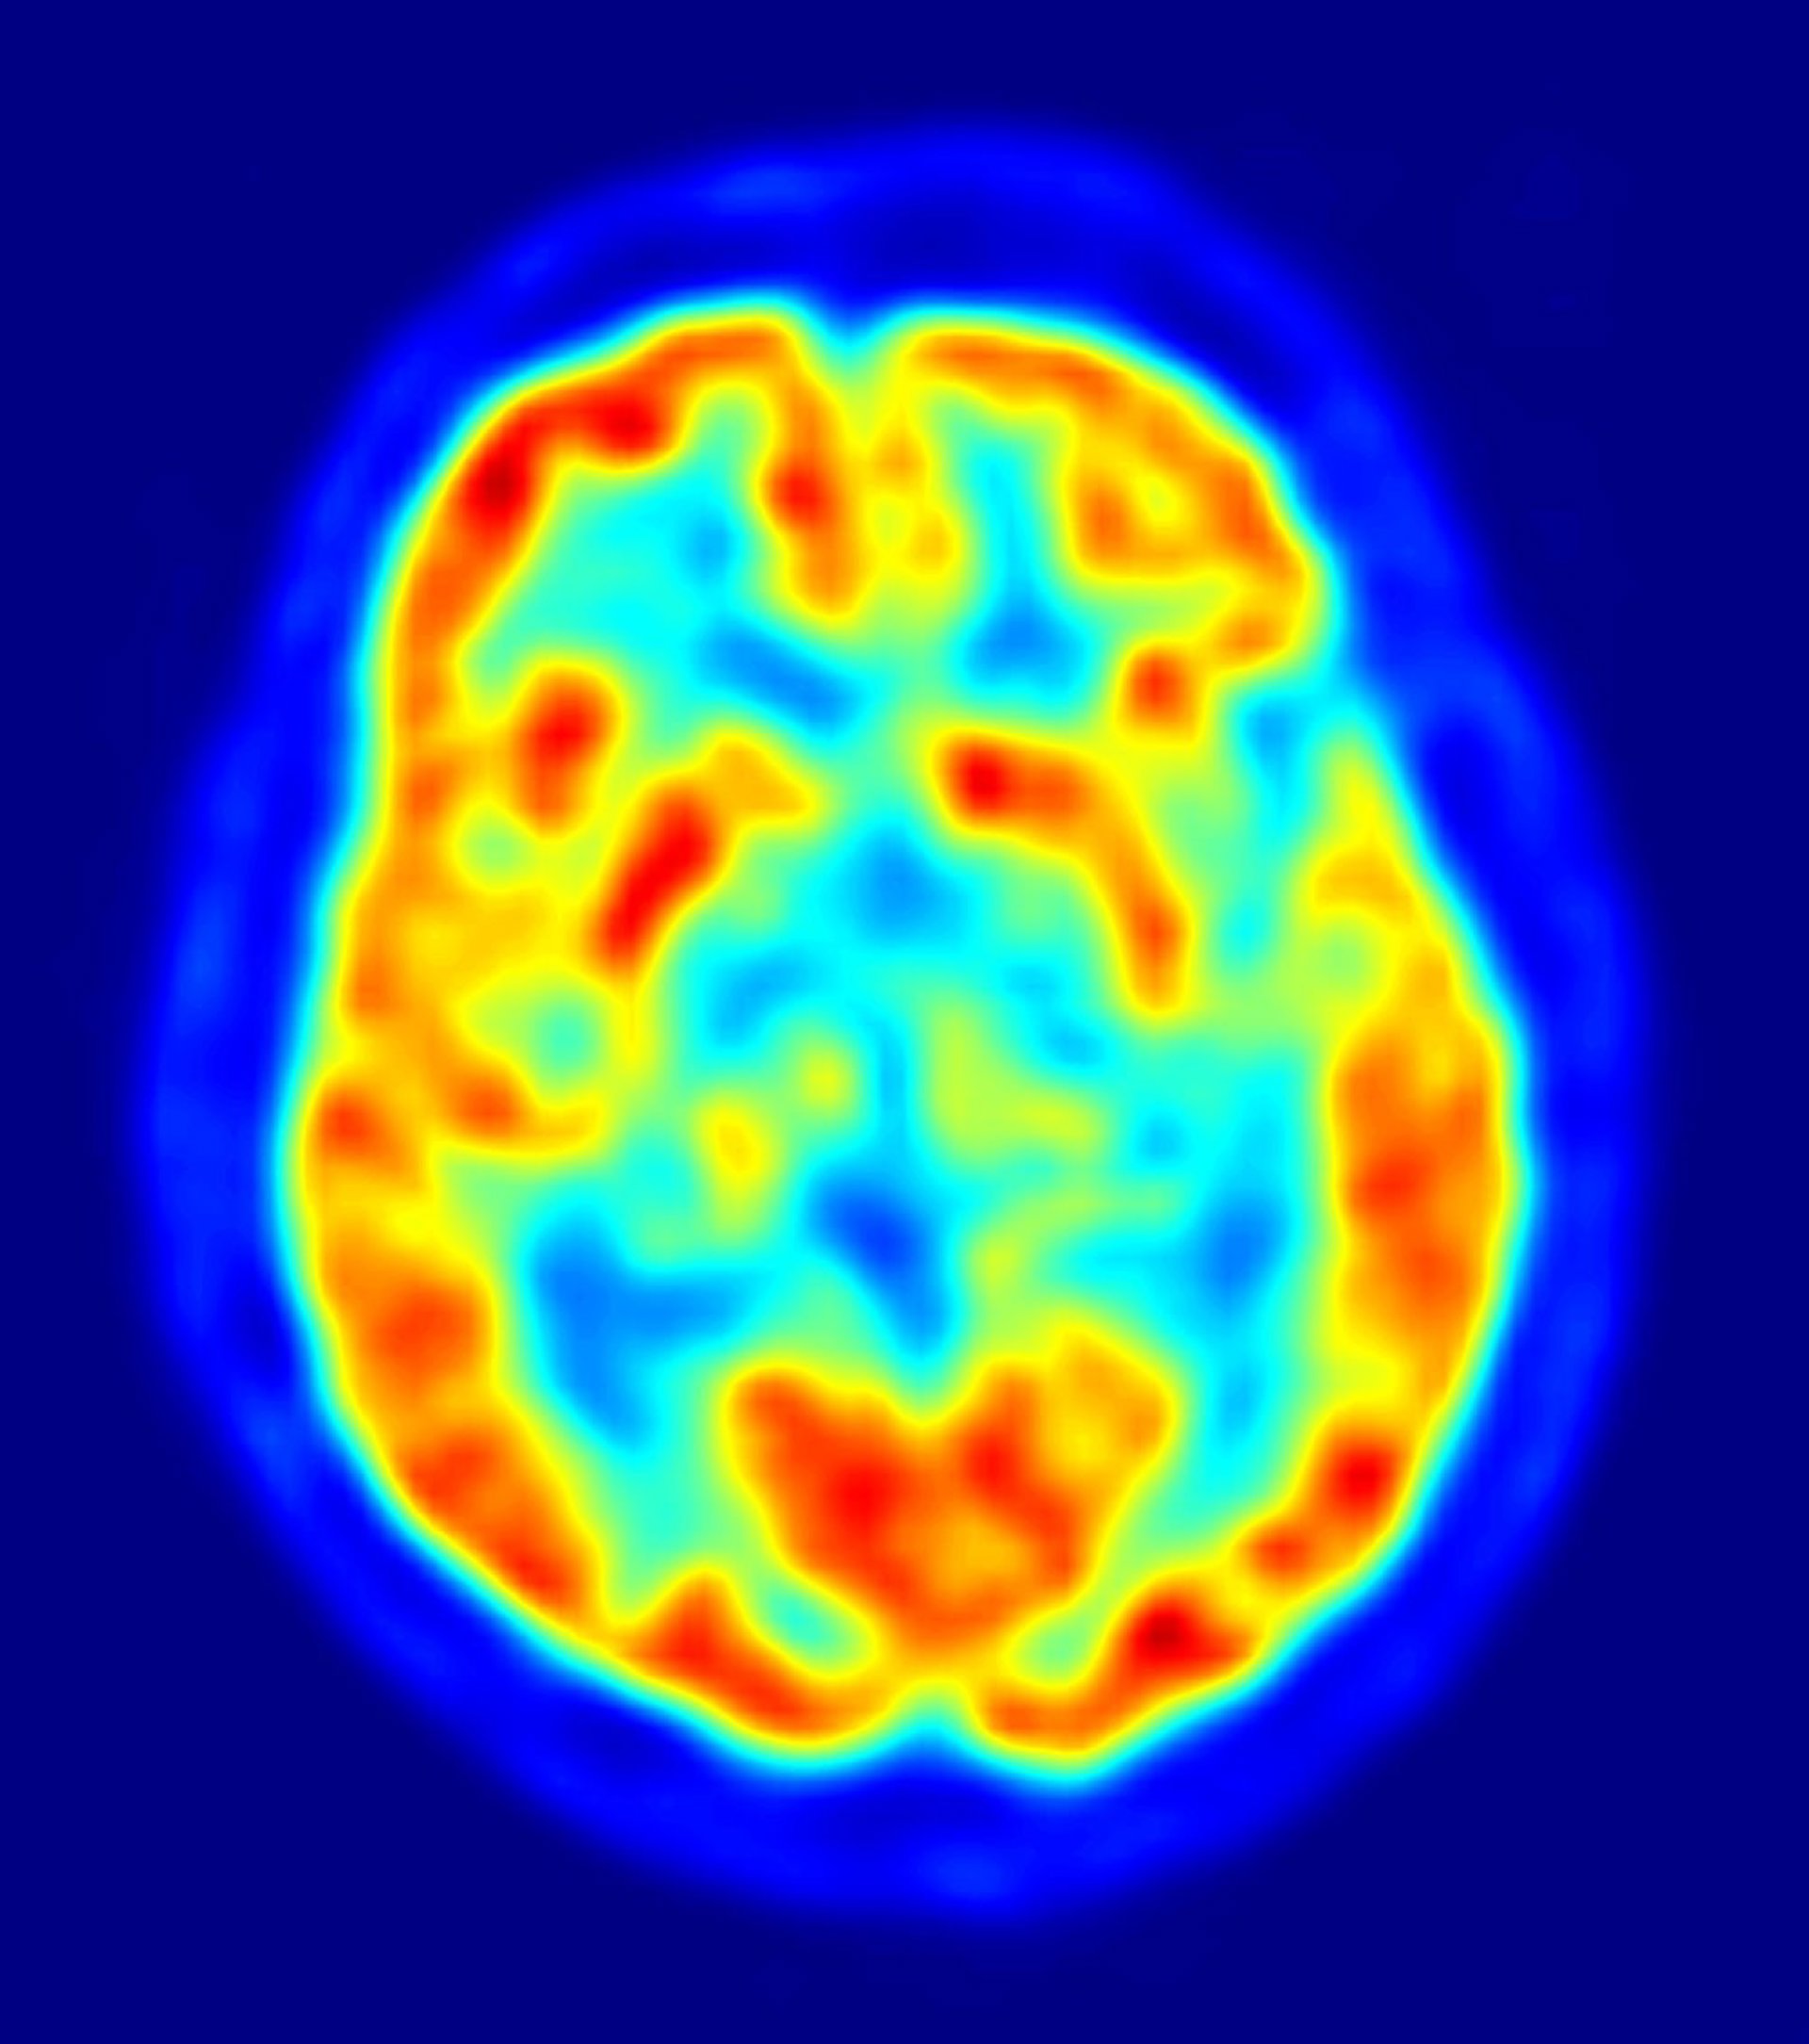

cerebro, recurso, neuronas

Este hallazgo, realizado a partir de una muestra del cerebro completo de una paciente y publicado en la revista 'Human Molecular Genetics', demuestra que la deficiencia de la proteína MLC1 en la superficie de las células está en la base de la enfermedad y que la GlialCAM es la proteína encargada de llevar MLC1 hasta las uniones celulares.